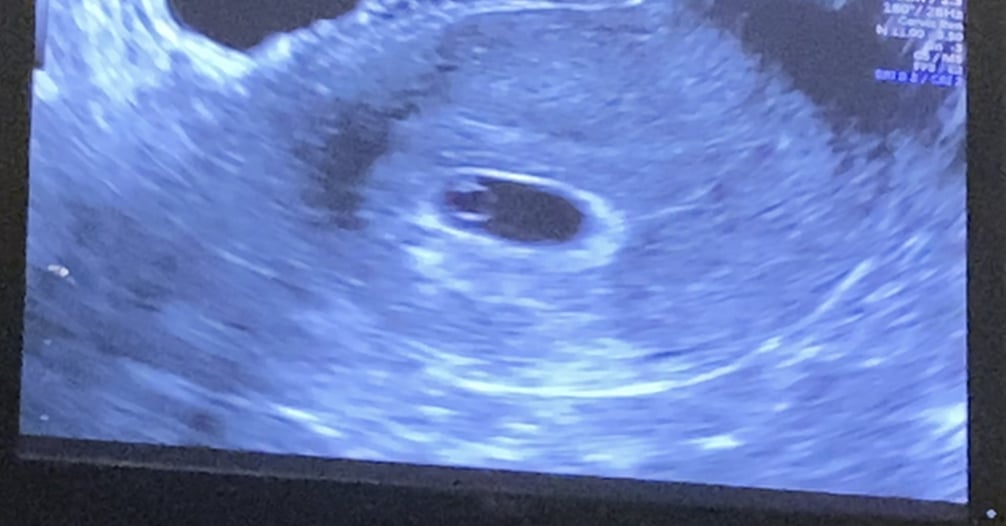

Anyhow, I could somewhat pinpoint from when we DTD (do the deed) and because I take ovulation test to also prevent pregnancy.. Worked for 16 months haha! Not a fail proof method, obviously. I did not get a positive ovulation test so that was no help at all! I thought that I was 6W5D during my ultrasound but all that showed was a gestational & yolk sac. Which would be fine if I were 5 weeks. But based on when I got a positive pregnancy test the very earliest I could possibly be is 6 weeks exactly otherwise a positive test wouldn't be possible.